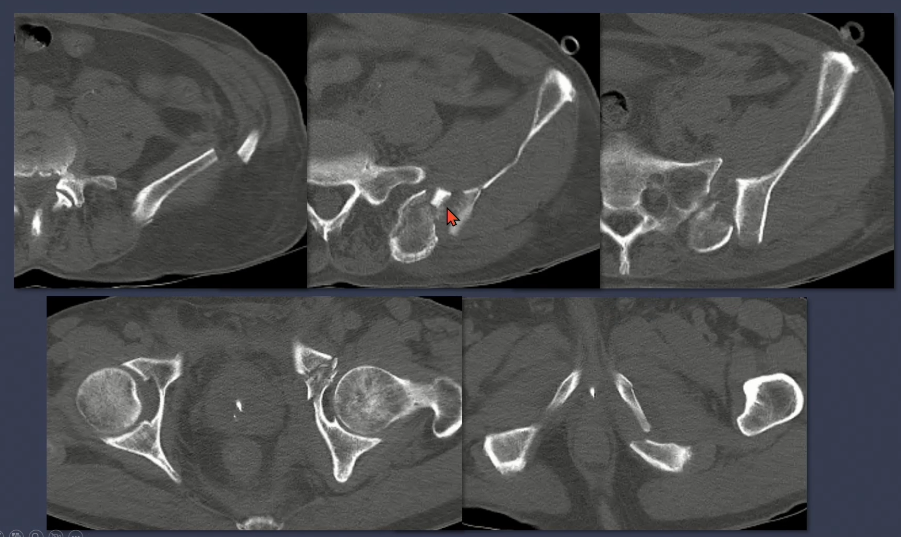

1. Anatomy & Young-Burgess classification

2. APC type

3. LC type

4. Vertical shear type